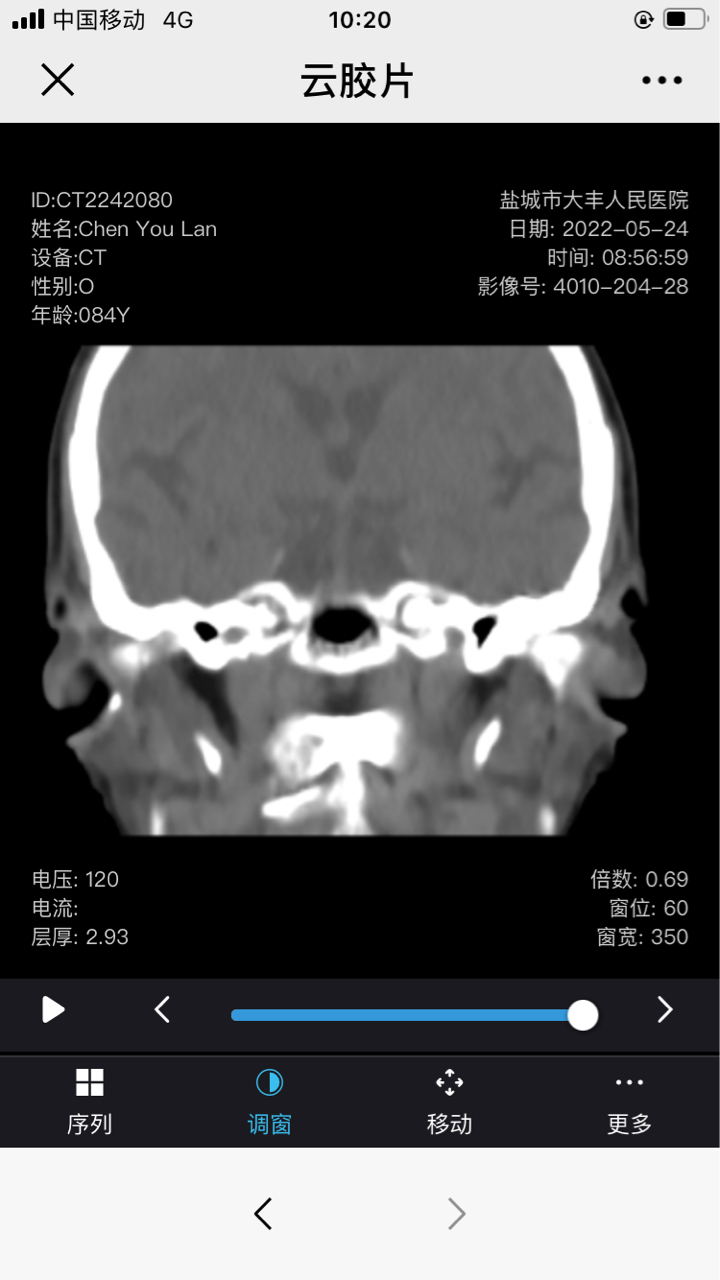

奶奶近两月鼻腔一直出血,有时带脓,初诊为鼻炎鼻窦炎,药物治疗效果不好。Ct也没说什么。活检说怀疑淋巴癌。急!

这是Ct报告